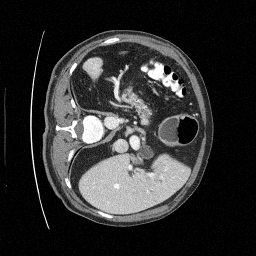

Training an NCSN on Abdomen CT - I

Figure 1: Some augmented example images from the training split.